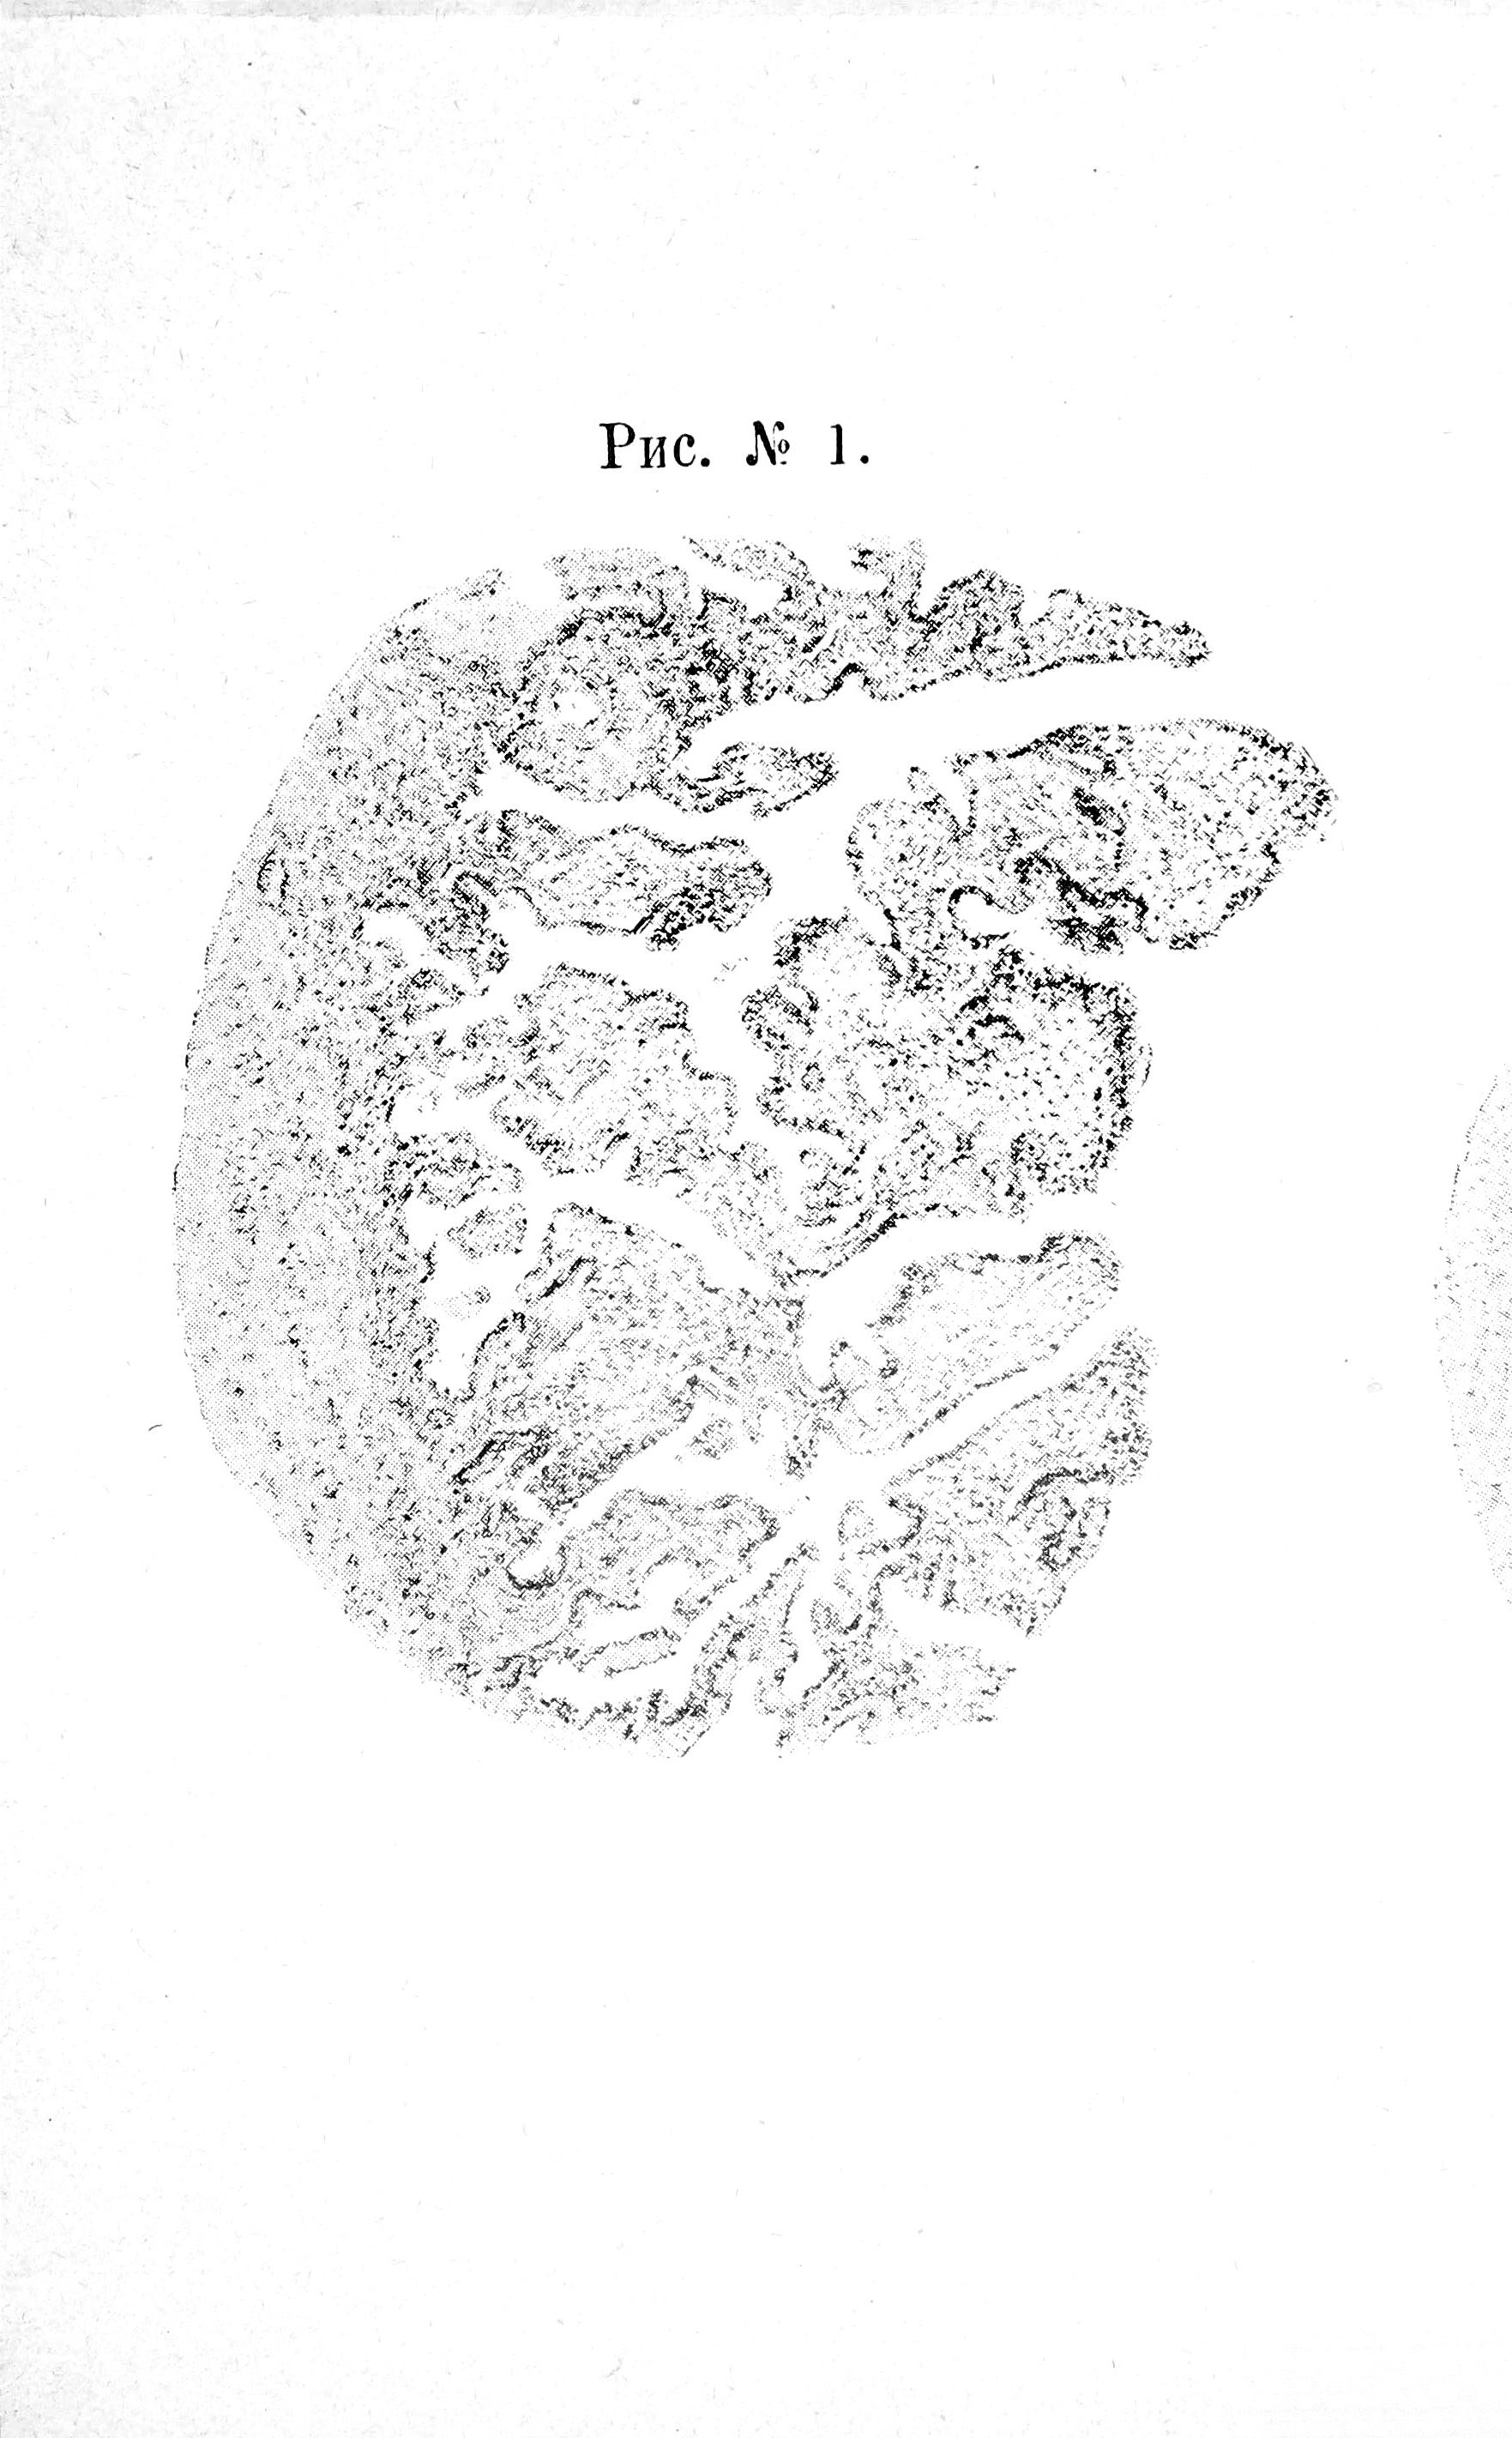

Складки слизистой оболочки при Salpingitis catarrhalis являются гипертрофированными, набухшими, съ большей или меньшей клѣточной инфильтраціей, сростаются между собою и обнаруживаютъ вышеописанную вѣтвистость, но менѣе рѣзко выраженную. Ворсинки иногда сильно утолщаются и колбообразно вздуваются, (см. рис. №3). На верхушкахъ складокъ эпителія пѣтъ, въ заворотахъ и карманахъ онъ остается въ цѣлости. Мышечный слой сильно развитъ соединительно тканные элементы отступаютъ на второй планъ. Болѣе или менѣе ясно выраженная мелко-клѣточковая инфильтрація въ видѣ кучекъ или полосъ.

Рис. № 3